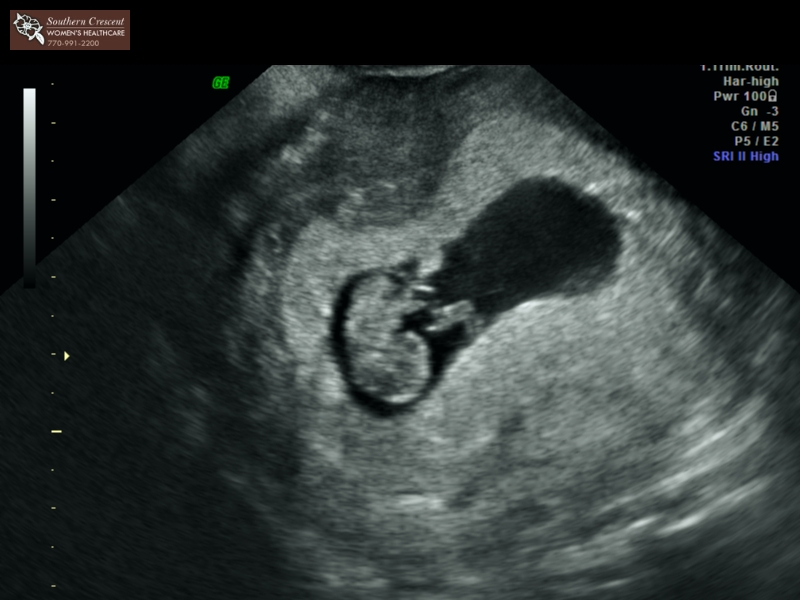

Here is our little bud from yesterday's u/s! SO relieved and excited to see that beautiful heartbeat (157 bpm). I was pretty on point with tracking my ovulation and knew I was 7w4d at the appointment. That's exactly what they measured me at too. However, they aren't budging on my O date and are going by my LMP, which according to them I'm more like 8w1d with a due date of May 6. I'm not budging on my end and will still be telling everyone my due date is May 10.